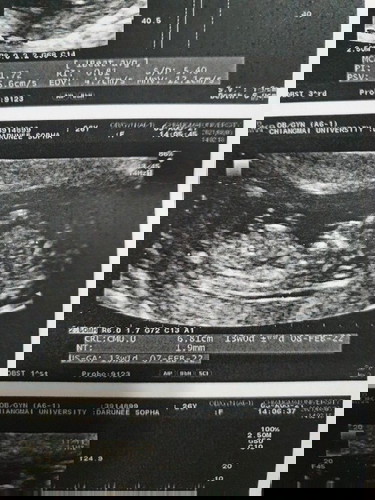

ปกติคนเลือดไม่จางจะมีอยู่ 4 คู่ แฟนเรามี 2 คู่ ส่วนเรามีแค่ 1 คู่ เลยเป็นคู่เสี่ยงธาลัสซีเมีย หมอเลยให้ทำการเจาะชิ้นเนื้อรก ในวันที่ 3 สิงหาคม อายุครรภ์ได้ 13 สัปดาห์ และหมอโทรแจ้งผลในวันนี้ วันที่ 10 สิงหาคม 14 สัปดาห์ หมอโทรมาแจ้งตอนเช้า ว่าน้องเป็นธาลัสซีเมียแบบเต็มตัวไม่สามารถตั้งครรภ์ต่อได้ ถึงจะตั้งครรภ์ต่อไปน้องก็จะบวมน้ำก็จะเสียชีวิตในที่สุด หมอให้ตัดสินใจเอาออกภายในอาทิตย์นี้ซึ่งเราทำใจไม่ได้มากๆ ใครมีประสบการณ์มาเล่าให้ฟังหน่อยนะคะตอนนี้กำลังตัดสินใจกับแฟนอยู่ ลืมบอก คนนี้เป็นคนที่สองแต่คนแรกเราเพิ่งหลุดไปตอน 6 สัปดาห์เมื่อตอนมกราคมที่ผ่านมา และเริ่มตั้งครรภ์ใหม่ในเดือนพฤษภาคม #หมอให้ยุติการตั้งครรภ์ #ขอถามประสบการณ์